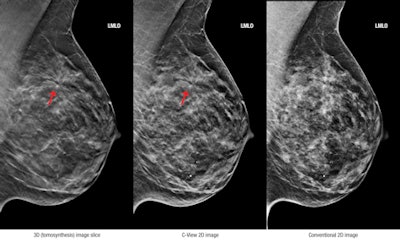

3D (tomosynthesis) image slice (left), C-View 2D image (center), and conventional 2D image (right). Images courtesy of Hologic.Other recent papers have demonstrated that women in their 40s are most likely to benefit from screening with DBT (a finding that could shape the debate over breast screening in younger women), and that women with dense breasts are another population likely to benefit.